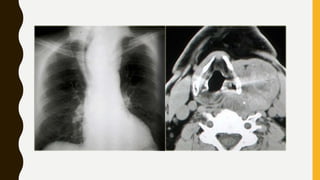

INVESTIGATIONS

• X-ray neck :AP & Lateral view

• CT scan : to look for retrosternal extension

INVESTIGATIONS • Thyroid functiontests • Ultrasonography (USG) • Fine needle aspiration cytology (FNAC) • Complete blood picture (CBP) • X-ray neck :AP & Lateral view • CT scan : to look for retrosternal extension • Thyroid scan-contains radioactive I • Indirect laryngoscopy : to see vocal cord mobility